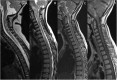

Relapsing demyelinating syndromes (RDS) in children encompass a diverse spectrum of entities including multiple sclerosis (MS) acute disseminated encephalomyelitis (ADEM), aquaporin-4 antibody associated neuromyelitis optica spectrum disorder (AQP4-NMOSD) and myelin oligodendrocyte glycoprotein antibody disease (MOG-AD). In addition to these, there are "antibody-negative" demyelinating syndromes which are yet to be fully characterized and defined. The paucity of specific biomarkers and overlap in clinical presentations makes the distinction between these disease entities difficult at initial presentation and, as such, there is a heavy reliance on magnetic resonance imaging (MRI) findings to satisfy the criteria for treatment initiation and optimization. Misdiagnosis is not uncommon and is usually related to the inaccurate application of criteria or failure to identify potential clinical and radiological mimics. It is also notable that there are instances where AQP4 and MOG antibody testing may be falsely negative during initial clinical episodes, further complicating the issue. This article illustrates the typical clinico-radiological phenotypes associated with the known pediatric RDS at presentation and describes the neuroimaging mimics of these using a pattern-based approach in the brain, optic nerves, and spinal cord. Practical guidance on key distinguishing features in the form of clinical and radiological red flags are incorporated. A subsection on clinical mimics with characteristic imaging patterns that assist in establishing alternative diagnoses is also included.